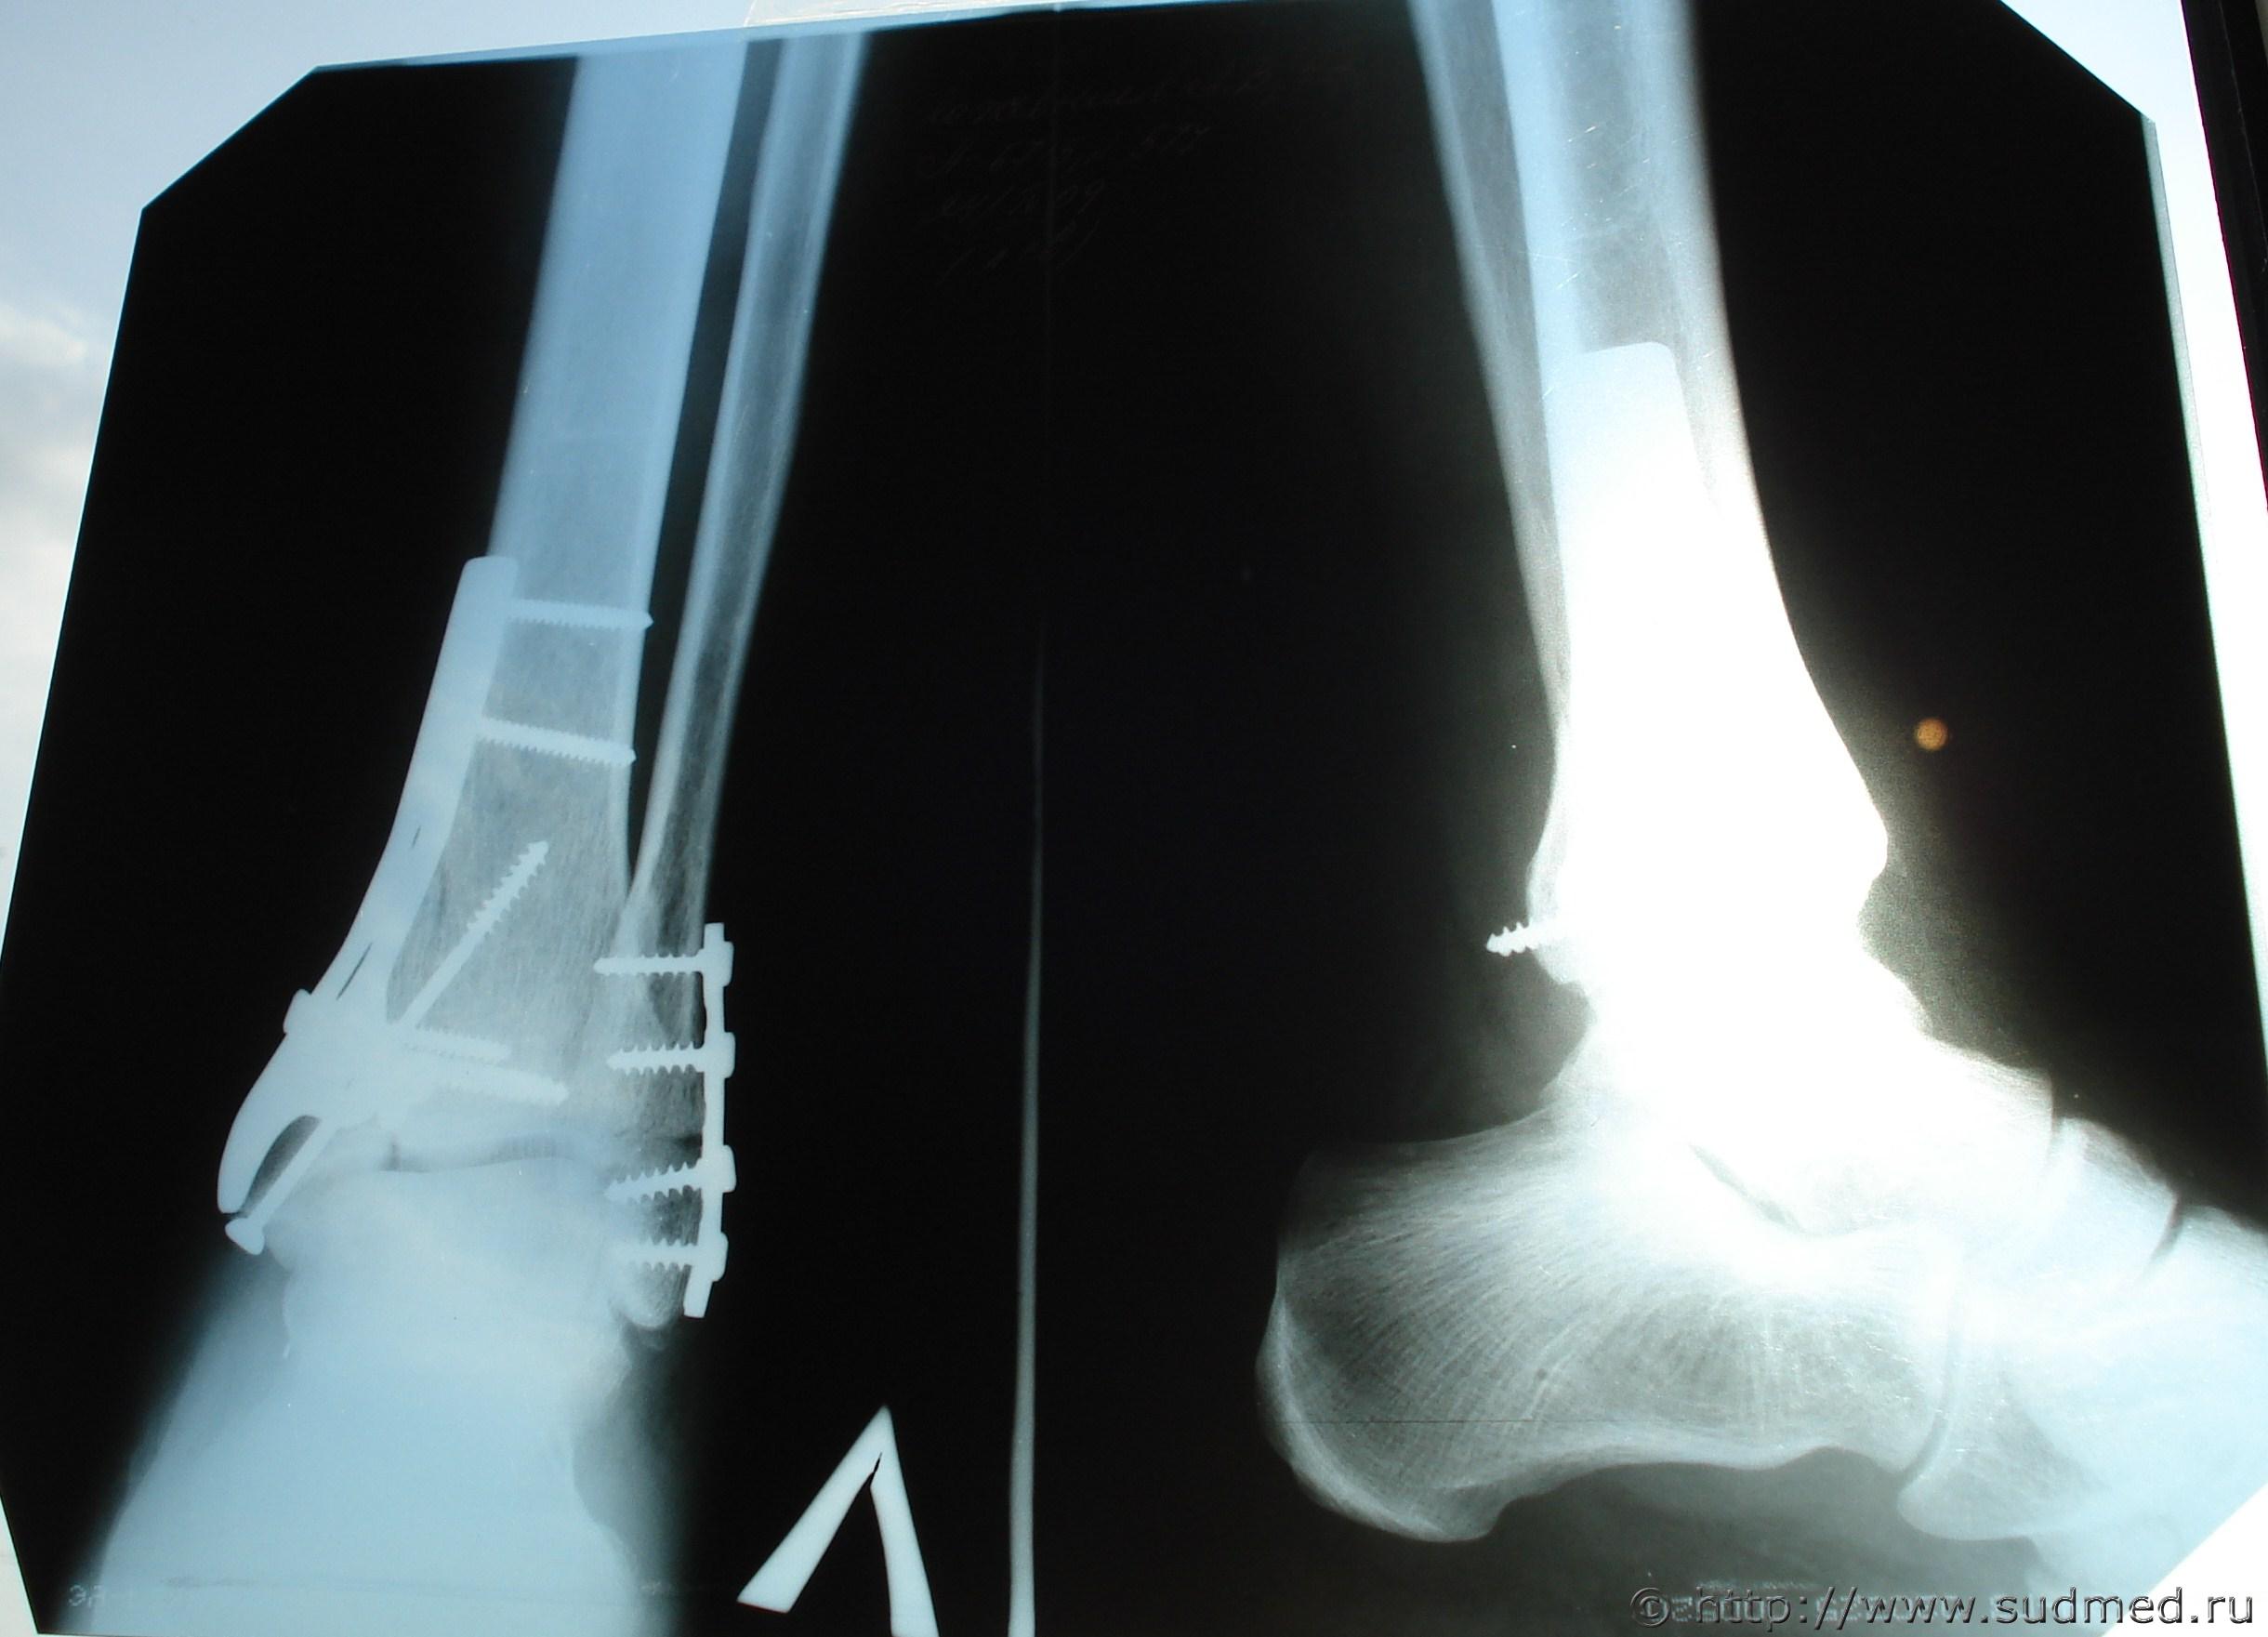

«Диагноз: Оскольчатый компрессионный внутрисуставной перелом дистального метаэпифиза с переходом на диафиз, заднего края б/берцовой кости, наружной лодыжки левой голени с подвывихом стопы кнаружи и кзади. Перелом 5 плюсневой кости левой стопы.

.. выполнена операция: открытая репозиция перелома, остеосинтез больше берцовой кости пластиной «кленовый лист» и винтами, остеосинтез наружной лодыжки реконструктивной пластиной пластиной и винтами».

Попробовал сделать копию снимка. Посмотрите, пожалуйста.

На снимках, мне кажется, видно, что перелом имеет место не только метаэпифиза (хряща), но и диафиза (тела большеберцовой кости), иначе её оперировавший врач не крепил бы металлической пластиной.

Извините, уважаемые эксперты, что представлен послеоперационный снимок (через 10 дней после травмы проведена операция). Остальная часть снимков находится в деле.

..другая часть снимков "потеряна" - поликлиника у меня их запросила и сразу потеряла, после приезда туда дознавателя.

Все переломы в пределах эпифиза и метэпифиза. Достоверных данных о переломе диафиза не усматриваю.

Согласен с уважаемым коллегой FILINом - переломы не переходят на диафиз. Значит, вред здоровью средней тяжести был выставлен правомерно.

3. Представлены рентгенограммы левого голеностопного сустава в двух проекциях (3) №№ 117, 118, 279 от 13.04.2009г. и 15.04.2009г. на имя К......, 43 лет, - рентгенологическая картина соответствует описанию указанных рентгенограмм в медицинских документах.

ПОВРЕЖДЕНИЕ у гр-на К...... , 1965 г.р.: Травма левого голеностопного сустава и левой стопы: закрытый оскольчатый компрессионный внутрисуставной перелом наружной лодыжки, перелом заднего края большеберцовой кости, дистального метаэпифиза большеберцовой кости, подвывих стопы кнаружи и кзади, закрытый оскольчатый перелом 5 плюсневой кости. Механизм данной травмы непрямой – форсированное подворачивание стопы подошвой кнутри с форсированным подошвенным или тыльным сгибанием. Данная травма образовалась, возможно, в условиях дорожно-транспортного происшествия, указанного в постановлении (наезд движущегося автомобиля на пешехода), в срок соответствующий 13 апреля 2009 года, и относится к повреждениям причинившим СРЕДНИЙ ВРЕД здоровью, так как вовлекла за собой длительное расстройство здоровья на срок более трех недель.

Снимки с полным охватом поврежденной области, хорошего качества, в двух основных проекциях. Для вывода о степени вреда здоровью достаточно и одного такого снимка.